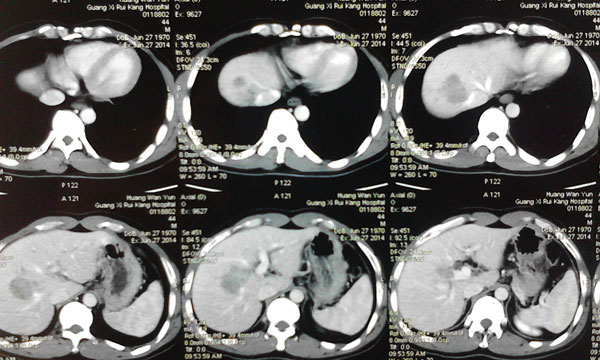

术后,黄先生被送回病房修养。在医护人员的精心治疗和护理下,患者病情稳定,仅有低热及轻度的疼痛,肝功能稳定。在术后第七天, CT检查发现左肝残肝增生明显,残肝体积已经达到右半肝切除的要求。

7月16日,韦杨年主任再次主刀,为黄先生施行右半肝切除术。手术非常顺利,术中无需阻断第一肝门,最大限度地保护了左肝残肝的功能。经过两次手术,成功切除右半肝,剖示肝脏肿瘤大小约8.0cm×5.0cm×5.0cm,肿瘤病理结果为:肝细胞肝癌。

第一次术后复查CT